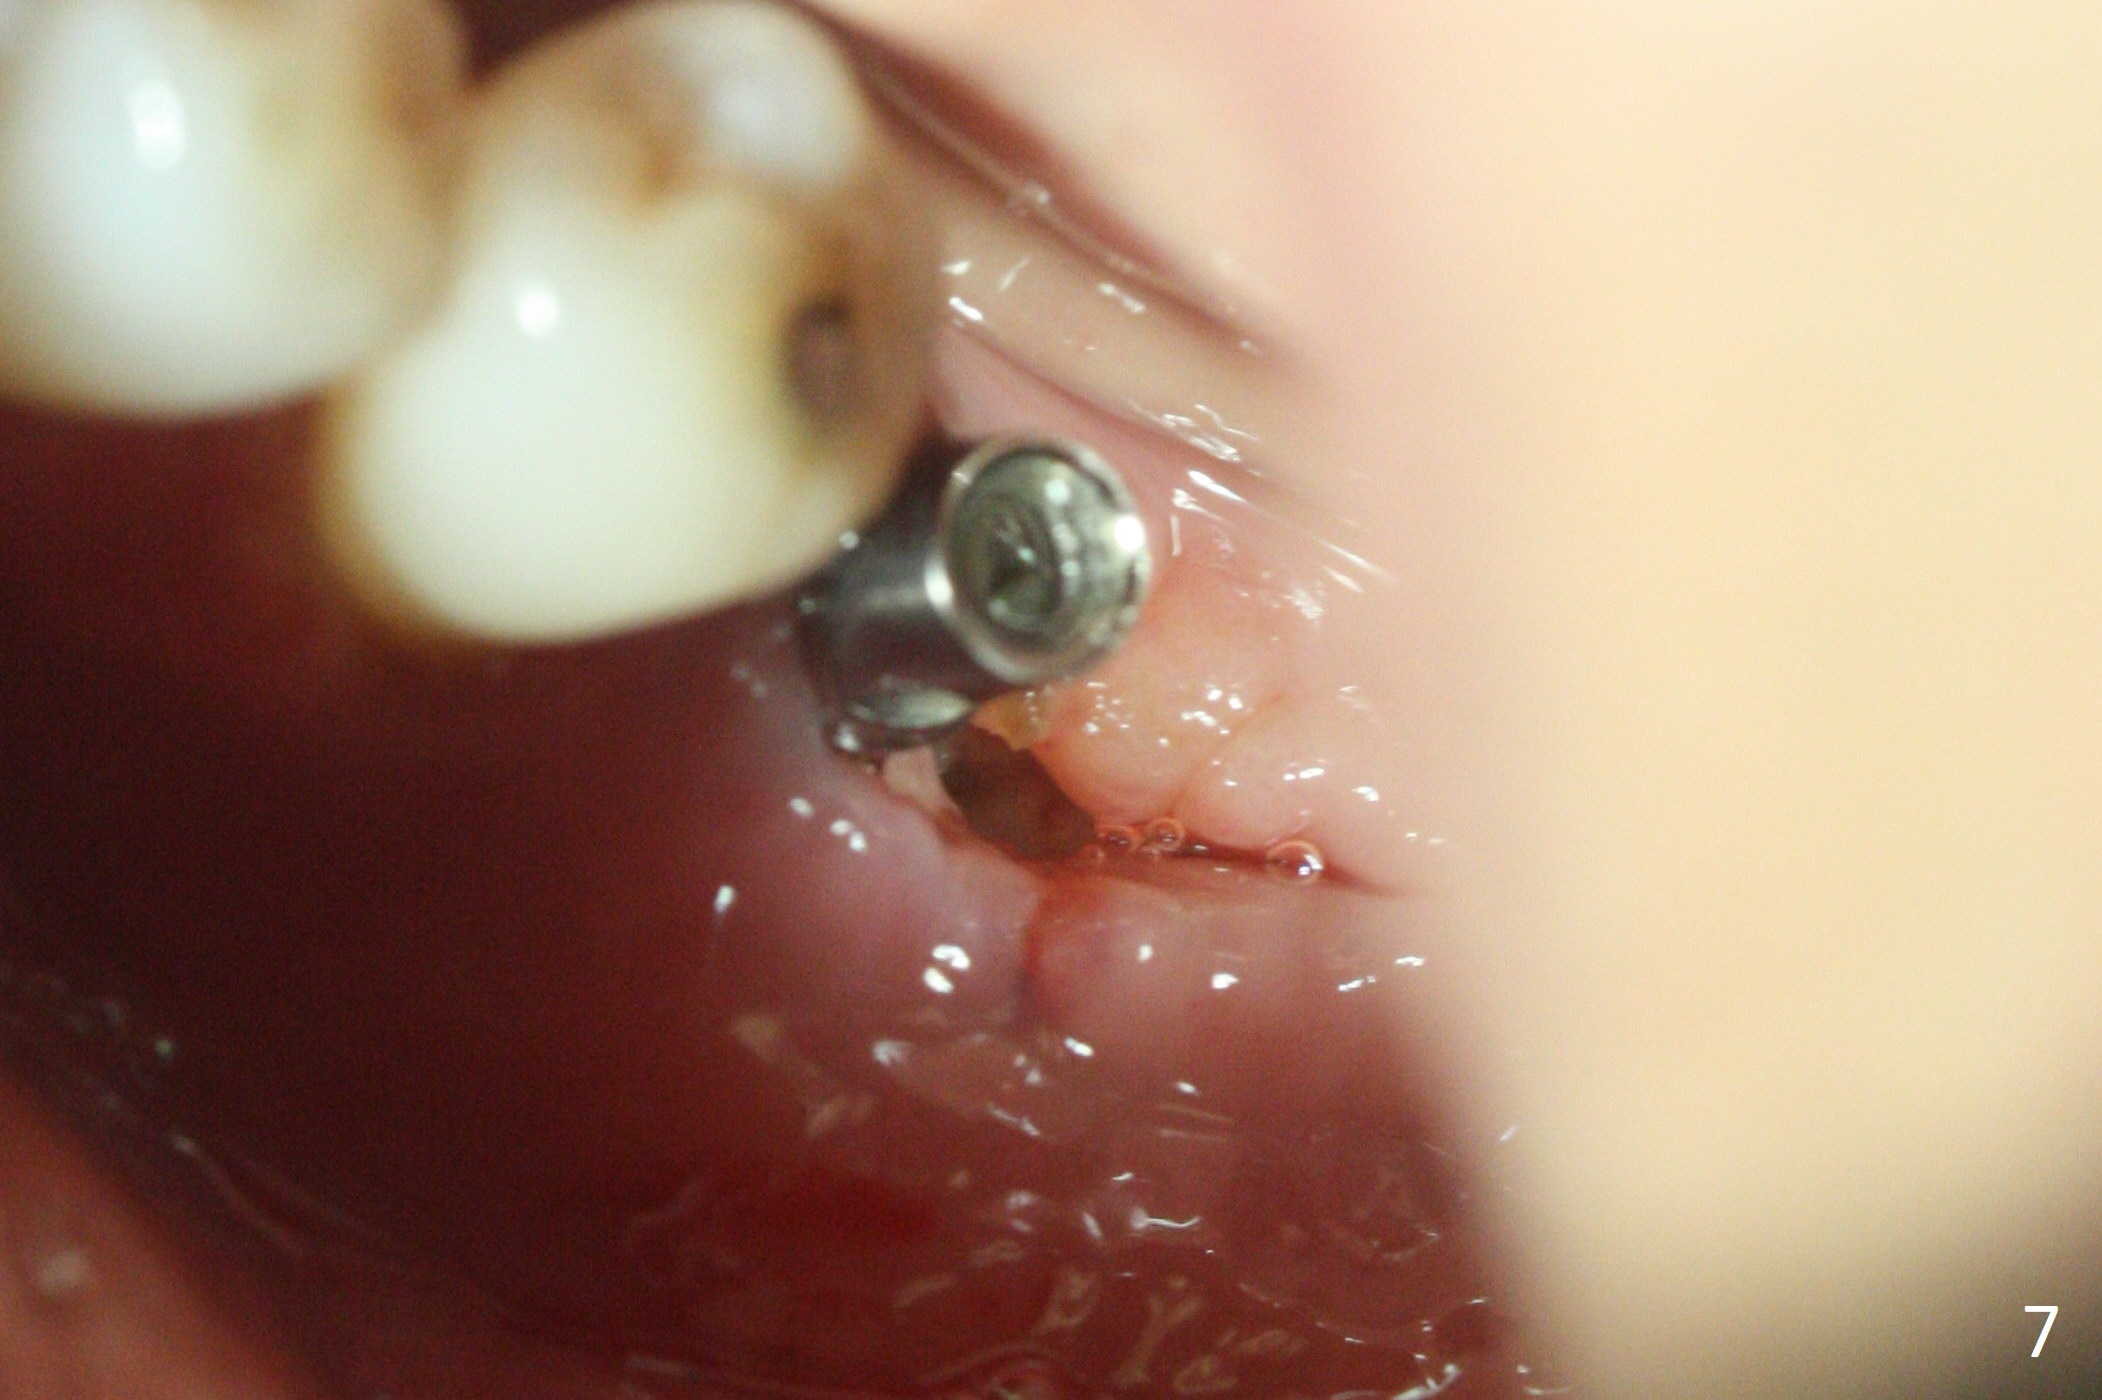

When the patient returns for treatment, the implant at #19 is mobile with tenderness (without purulence, Fig.1). She finally agrees to have CT taken (Fig.2,3 (coronal section (L: lingual))). The implant is removed after several carpules of cocktail anesthetics for infiltration and one carpule for block. Osteotomy is initiated in the mesial slope of the defect (Fig.2,4). The advantage of immediate implant re-placement is wide bone at the intended area (Fig.3). After change in trajectory (compare Fig.4 (4x11 mm dummy implant) and Fig.5), a 4.5x9 mm IBS implant is placed with insertion torque of 50 Ncm (Fig.5); with Osteogen plug placed in the distal defect, allograft (*) is placed immediately distal to the implant. With the longest cuff available (4 mm), the margin of the abutment (4.5x4(4) mm) is equi-crestal (>). When the 9 mm long implant is placed deep, the coronal threads of the implant are distally exposed (Fig.6 between arrowheads) less than those of the 11 mm one placed superficial (Fig.2). Intraoperative socket hemorrhage is controlled by packing gauze saturated with Epinephrine 1:50,000. The patient chooses not to take Medrol Dose Pack for postoperative edema. She removes periodontal dressing herself prematurely. The socket wound dehiscence is noted the first postop visit (7th day). Fig.7 is taken 9 days postop before re-suturing. The patient insists on removing the implant with dull pain. Three months 10 days postop, she returns with loss of the abutment and a fistula (Fig.8). In fact there is bone formation distal to the implant. Torque wrench has to used to remove the implant.